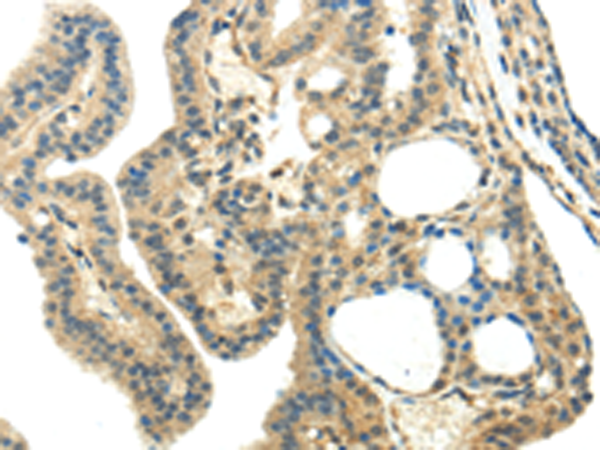

分类: 科研抗体货号: P12419别名: PHA2B; PRKWNK4应用: IHC反应种属: Human, Mouse, Rat